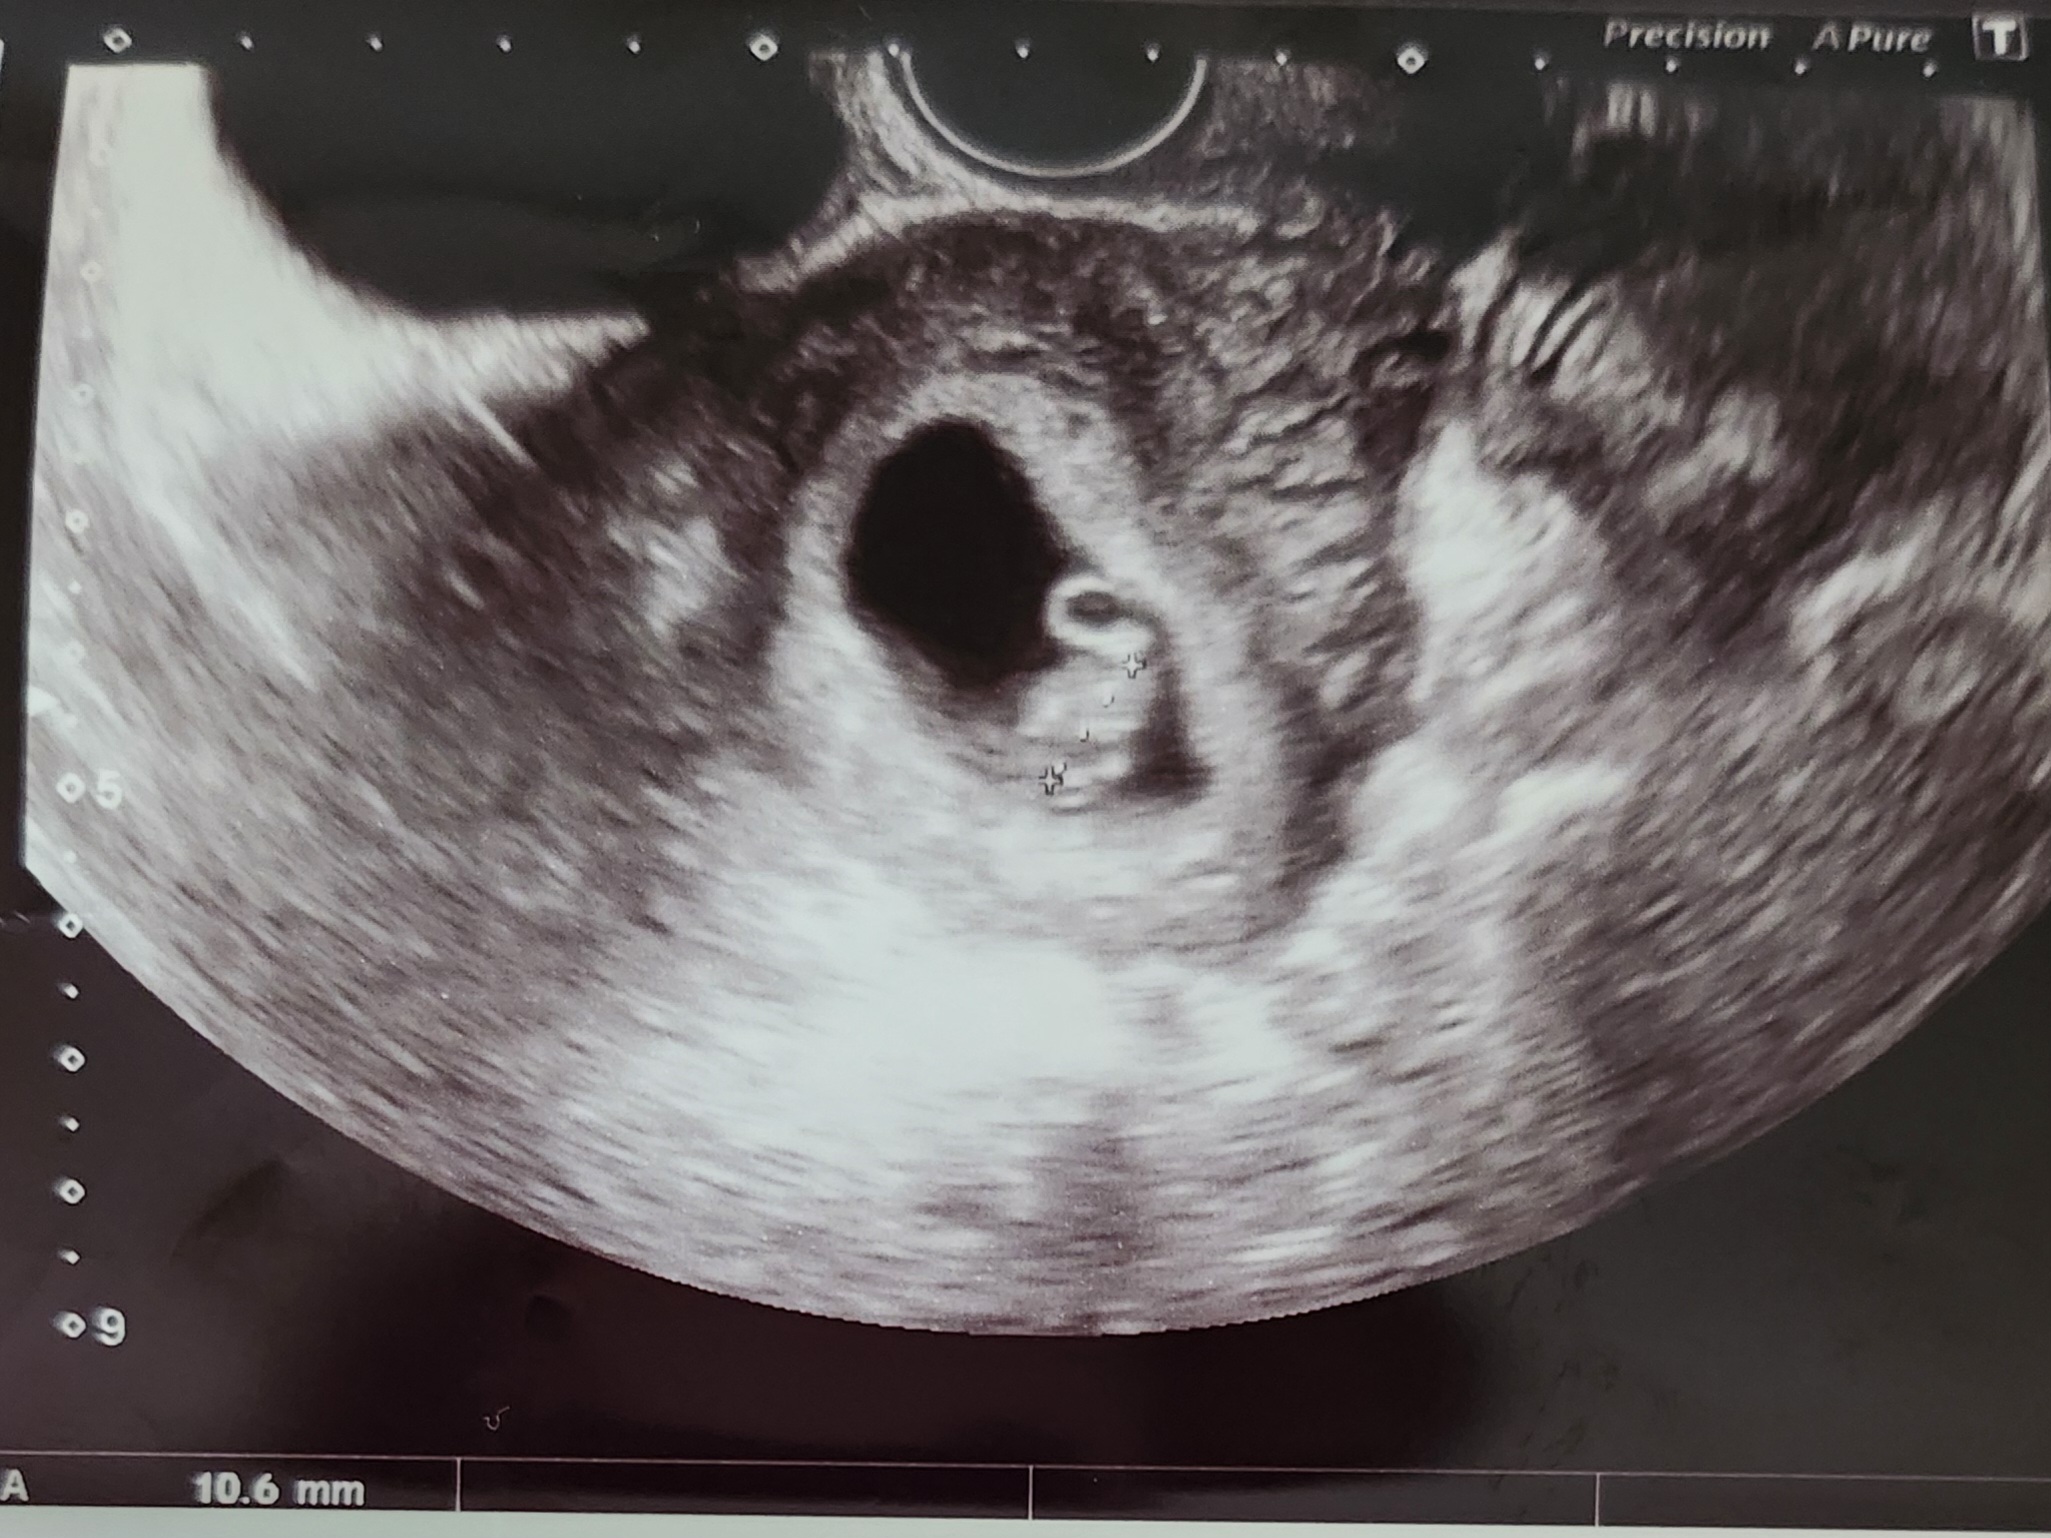

드디어 초음파 아기 만나고 왔어요

근데 해외라서 제가 보는 화면도 없고 지난번엔 커텐 사이로 의사화면 봤는데 이번엔 제대로 닫아서 하나도 못봤어요ㅜㅜ 말로만 건강하네요 심장 잘 뛰네요 듣고 초음파 사진만 받았는데 화질이....ㅋㅋㅋㅋ 그래도 둘째라고 대충 동그란건 난황 밑에 크기 잰건 아가라고 알아봤답니다 근데 살은 벌써 2키로나 쪘는데 아가는 생예기준보다 작네요 허허ㅋㅋㅋ